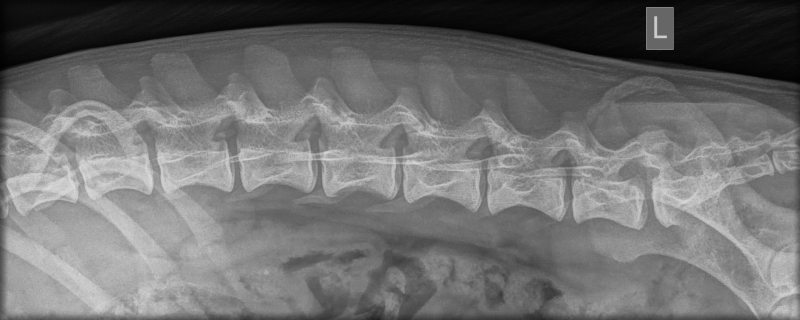

- Vertèbres lombaires : pas de 8e vertèbre lombaire, aucune anomalie